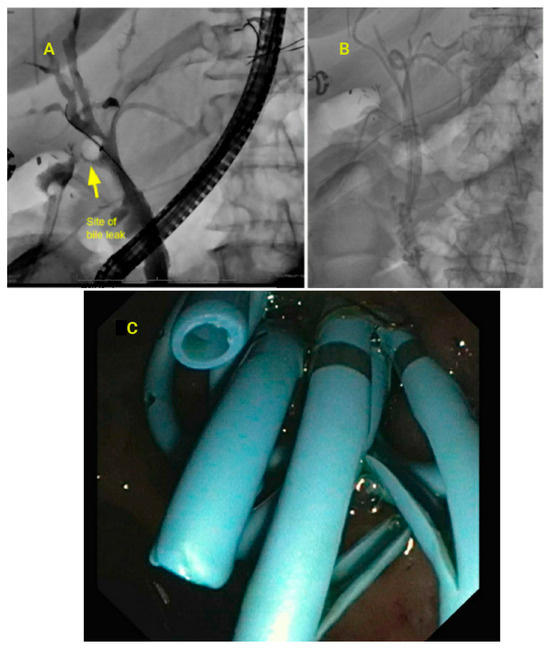

3.9. Bile Leak and Strictures

- Adler, D.G.; Papachristou, G.I.; Taylor, L.J.; McVay, T.; Birch, M.; Francis, G.; Zabolotsky, A.; Laique, S.N.; Hayat, U.; Zhan, T.; et al. Clinical outcomes in patients with bile leaks treated via ERCP with regard to the timing of ERCP: A large multicenter study. Gastrointest. Endosc. 2017, 85, 766–772. [Google Scholar] [CrossRef]

- Wang, A.Y.; Ellen, K.; Berg, C.L.; Schmitt, T.M.; Kahaleh, M. Fully covered self-expandable metallic stents in the management of complex biliary leaks: Preliminary data—A case series. Endoscopy 2009, 41, 781–786. [Google Scholar] [CrossRef] [PubMed]

- Lalezari, D.; Singh, I.; Reicher, S.; Eysselein, V.E. Evaluation of fully covered self-expanding metal stents in benign biliary strictures and bile leaks. World J. Gastrointest. Endosc. 2013, 5, 332–339. [Google Scholar] [CrossRef] [PubMed]